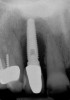

Figure 12  (Case 2) Initial radiograph of compromised implant No. 7.

Figure 12

Figure 13  (Case 2) Clinical presentation of No. 7 implant. Note discrepancy in crown length due to bruxism.

Figure 13

A 53-year-old woman presented with a failing implant in the No. 7 site (Figure 12 and Figure 13). Her desire was to eliminate infection and preserve esthetics. A team effort between the periodontist and restorative dentist to advocate for additional restorative dentistry as well as manage the patient’s expectation of time required was essential. In addition, the patient needed to have realistic expectations of a compromised outcome. Both the restorative dentist and the periodontist informed the patient about the difficulty of achieving this with acceptable esthetic results. Mutual emotional and technical support was required to successfully complete this case, from initial grafting of the defect to placement of anterior restorations (Figure 14 through Figure 23).